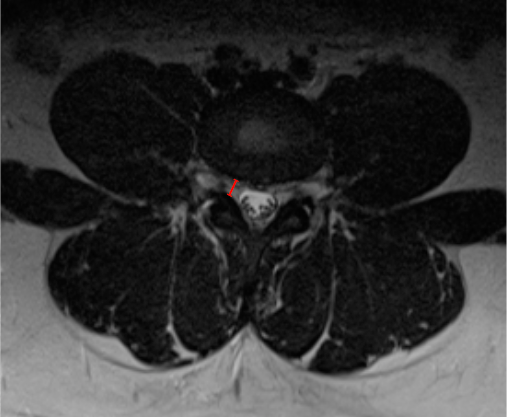

• Corroborate with axial T2 images to assess root compression or obliteration of perineural fat.

• Severe stenosis is typically associated with loss of perineural fat and direct nerve root compression.

• Height reduction reflects disc collapse, whereas width reduction reflects facet and osteophyte encroachment.